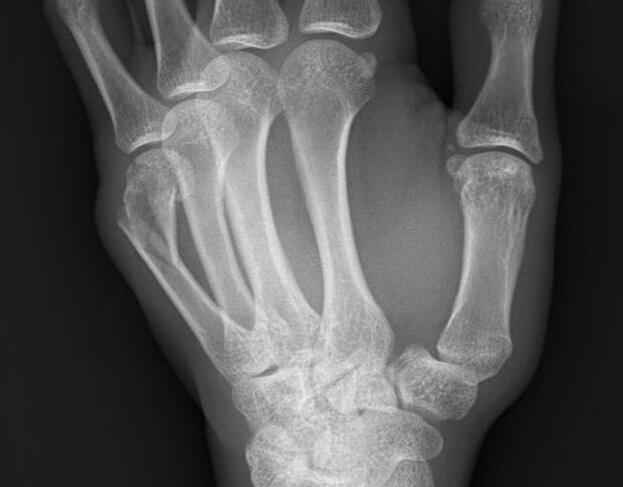

年轻人年轻气盛,喝酒后闹别扭,心情不爽,用手握拳捶墙的应该很多吧。但是做做样子就行,可别用力太过,用力太猛自己会受内伤的。例如下面小伙子用力捶墙后出现手掌骨颈骨折,由于常见于拳击运动员,所以也叫“拳击手骨折”。

拳击手骨折常常是远端向掌侧移位,骨折端向背侧成角。